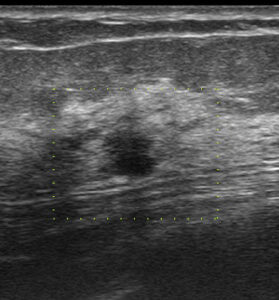

初回の検診エコー(今回送られてきたもの)

縦長! 不整型!

これ(去年に何もなかったのに、しかも60歳代)で要精査に何故しない!!

別角度

やっぱり、どう見ても「癌疑い」

何で、カテゴリー2で要精査としなかったのだろう。